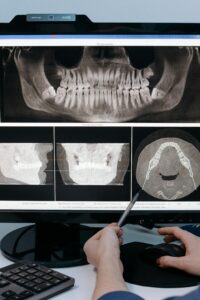

Reviewed by Richard Dawson, DMD — General & Implant Dentist, ICOI Fellow, Smile Science Dental Spa What Are Zygomatic Implants? Zygomatic implants are extra-long titanium implants anchored in the zygomatic bone (the cheekbone) rather than the jaw. While conventional dental implants are 8 to 16 mm long and placed entirely within the alveolar bone of […]

Read Zygoma Implants: A Definitive Guide